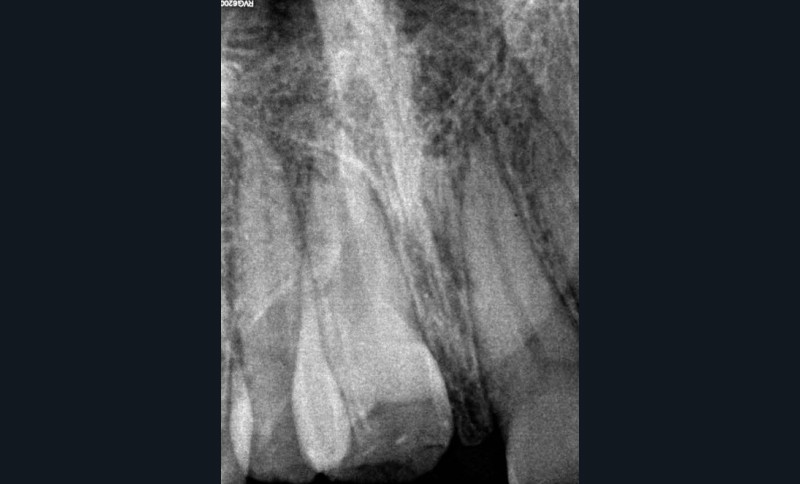

Yasmine, une adolescente de 14 ans et demi, en bonne santé générale, consulte en urgence vers 10h30, à la suite d’une chute s’étant produite le matin même en allant à l’école vers 8h. Les figures 1 et 2 montrent respectivement les vues cliniques et radiographiques. La mère nous rapporte un antécédent de trauma sur les incisives centrales, il y a quelques années.